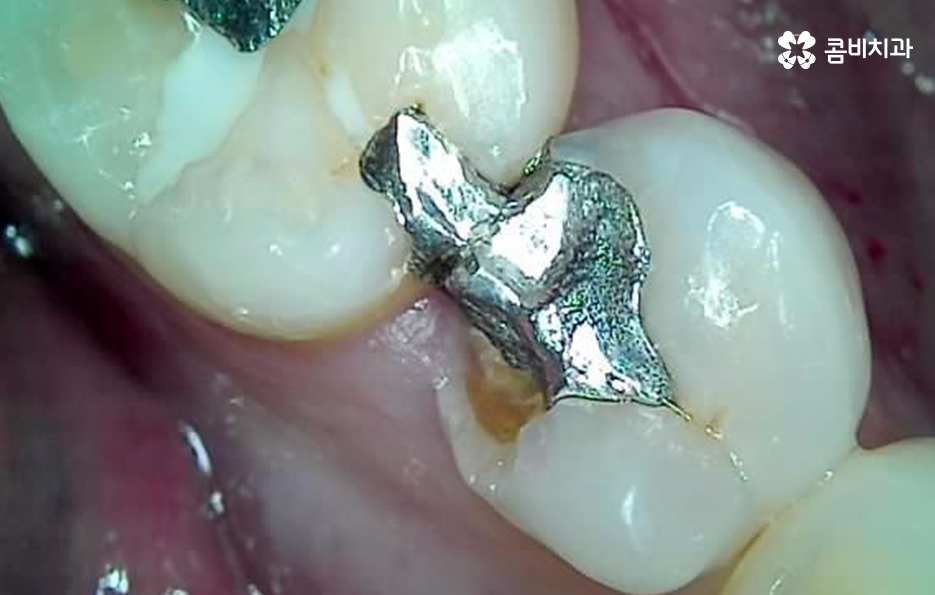

특히 위 환자분의 사례처럼 아말감의 경우에는 빠르고 저렴한 치료 자체는 장점이 있지만 아말감의 특성상 주변 치아가 변색될 우려부터 치아와의 접착이 좀더 빠르게 약해질 우려가 있는 보철물이며 아말감이 조금씩 깨지면서 틈 사이로 충치가 발생되는 사례도 많기 때문에 어금니 충치 깨짐의 경우 보편적으로 보철물 내부에 2차 충치가 발생되면서 치아 내부의 충치가 드러나는 경우가 많고 충치가 없던 경우에는 기존의 치아에 지속적인 마모와 손상이 거듭되다가 치아의 내구성이 약해져서 결국 깨지면서 문제가 드러나는 경우가 많을 거예요